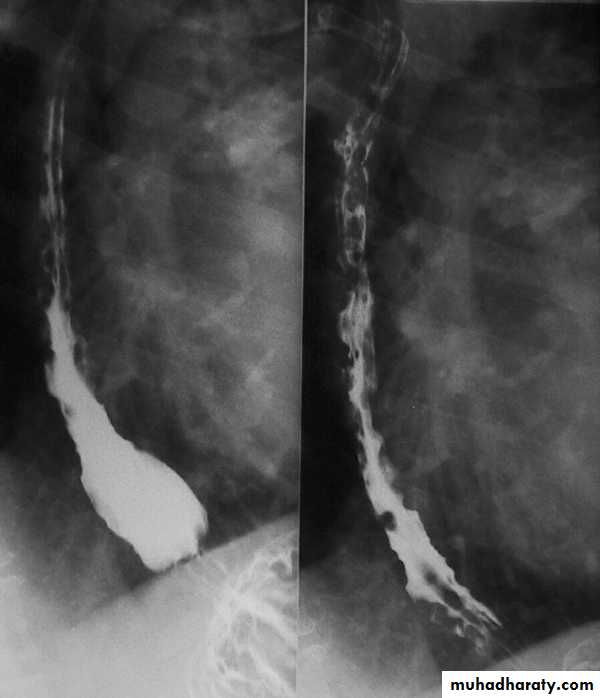

Narrowing :

the narrowing is Constant Short length (confined to cardia).

Regular and smooth.

No shouldering sign.

Tapering (Tip of pencil , cigar shape) Under left dome of diaphragm.

DILATATION (Sac like in proximal part )

Undulating or spiky out line due to sluggish peristalsis.

Non- homogeneity of Barium due to food particles.

Air Barium level.

CXR shows widening of mediastinum.

Absence of fundal gas shadow.

Basal fibrosis in lungs due to repeated aspiration pneumonia .

LEFT: Dilated esophagus (arrows) appears as long, well-defined structure paralleling heart RIGHT: Dilated esophagus usually deviates to right. Narrowing (arrow) at hiatus.